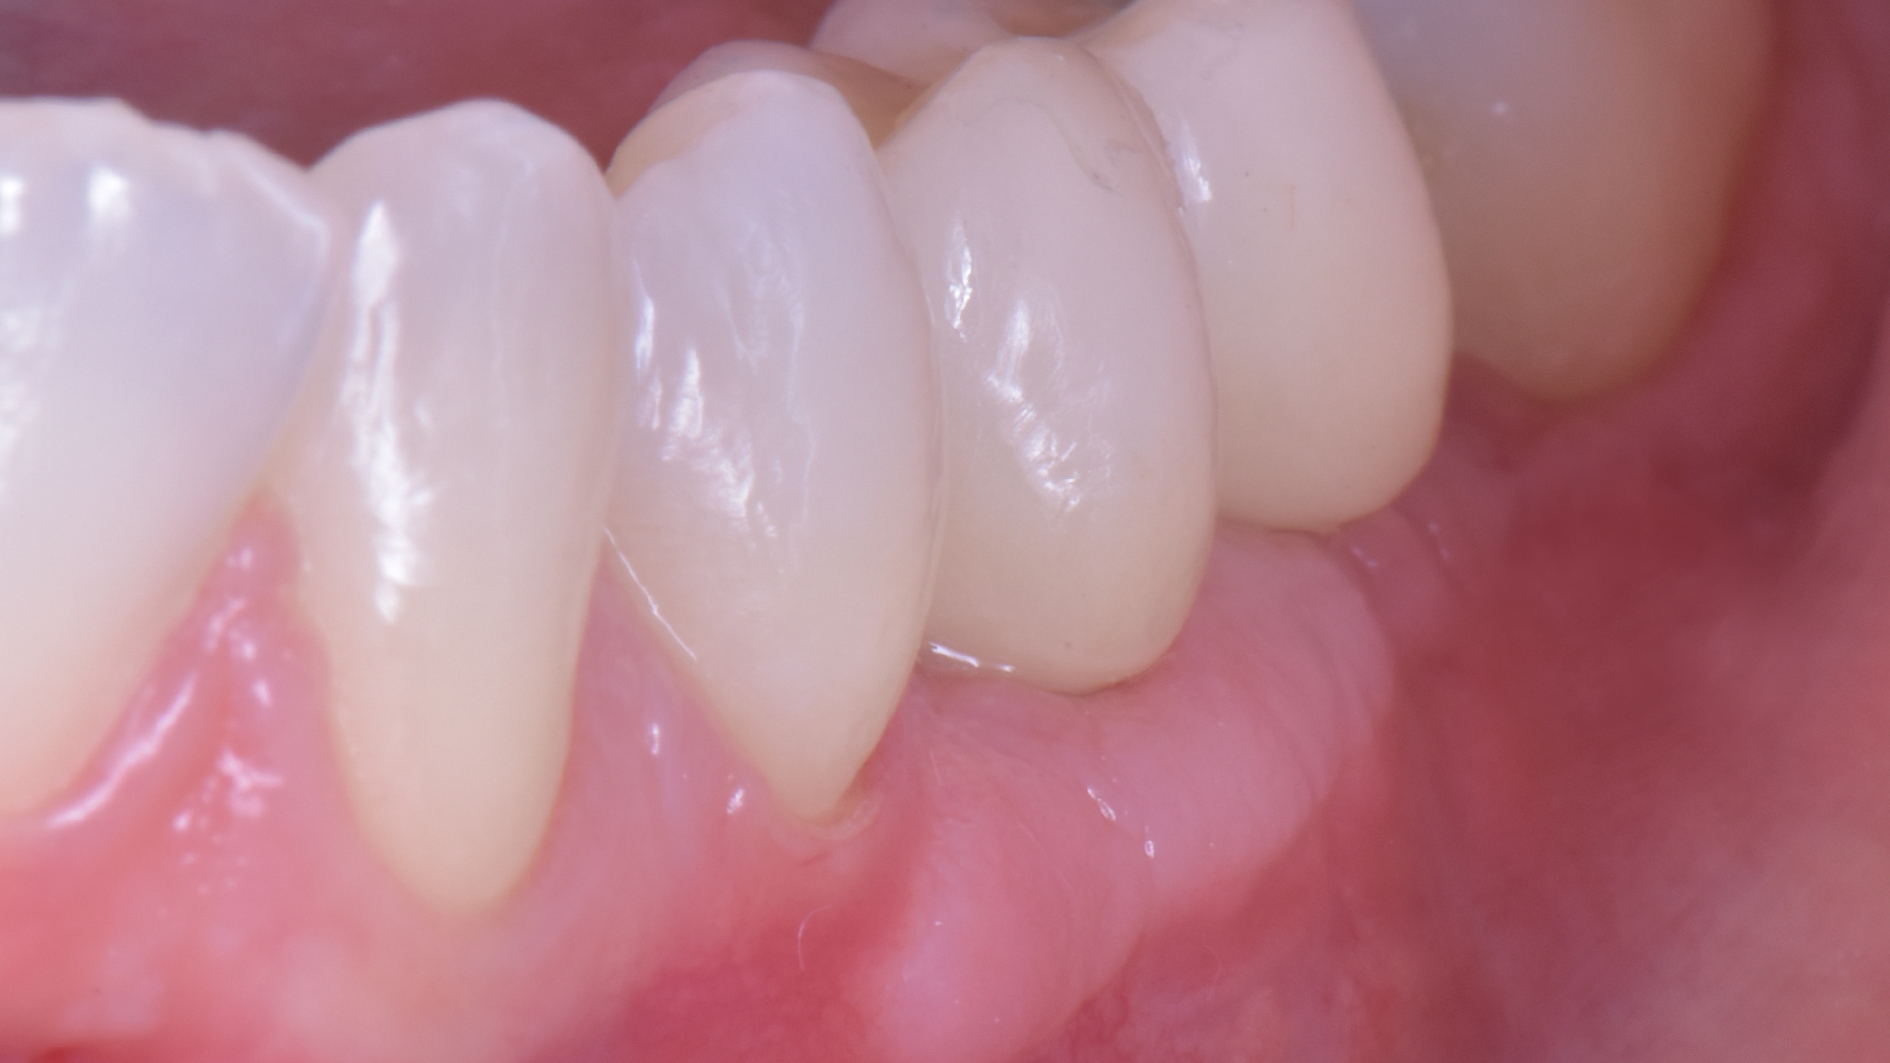

Ecco i risultati dei due casi:

Nel secondo, ad esempio, un ponte non è paragonabile alla soluzione ricostruttiva che ho attuato. Neanche lontanamente! Quindi è inutile dire

Perché il ponte non era la terapia giusta in questo caso! PUNTO! Avrebbe richiesto un sacrificio biologico drammatico in una ragazza di 28 anni e avrebbe portato ad un estetica diciamo “discutibile” vista la mancanza di volume rosa residuata dopo la rimozione dell’impianto infetto.

O puoi riabilitare la paziente adeguatamente:

Ma per fare questo non ci sono polverine magiche di osso di dinosauro o impianti di un millimetro. Ci sono anni di studio, sudore e sangue (E SGUARONE!!) per noi… e un VAS 2 per la paziente!!!!!!! ?